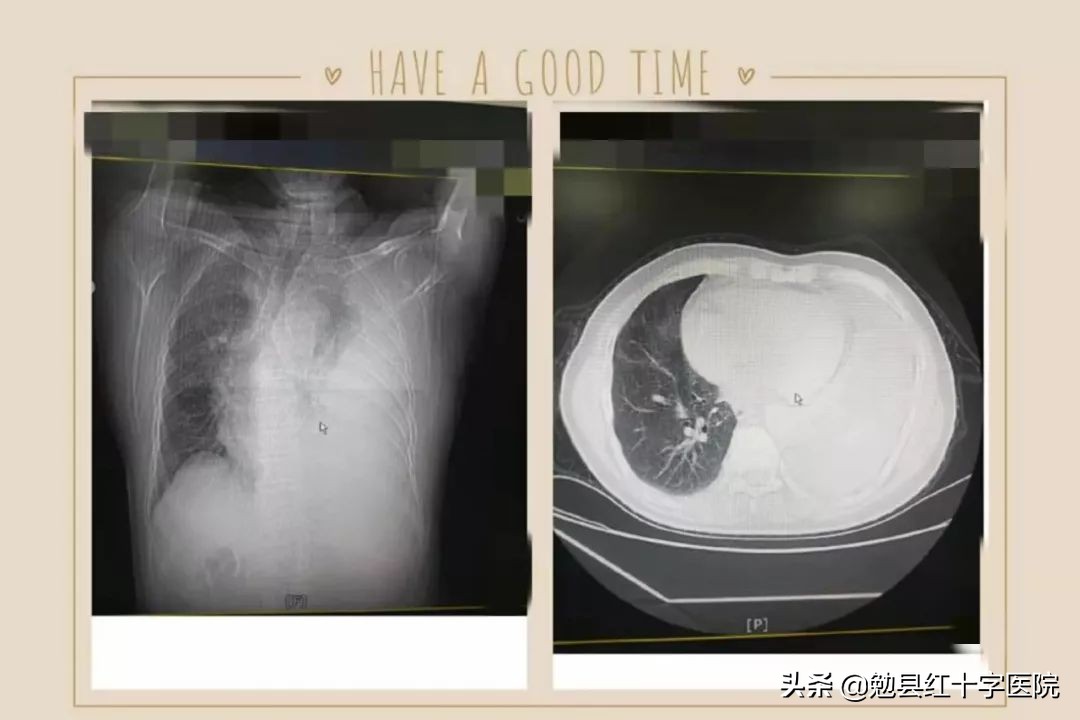

CT提示左侧大量胸腔积液,纵膈右偏,大量胸腔积液导致肺压缩膨胀不良

治疗前

立即安排为患者行胸腔穿刺术,抽出540ml淡黄色液体,并留取标本送检,抽液后的当天患者气喘明显好转,可平卧,治疗期间,再次为患者行胸腔穿刺置管引流术,并联合药物治疗。复查胸部CT时积液明显减少,症状明显缓解,左侧胸痛基本消失。